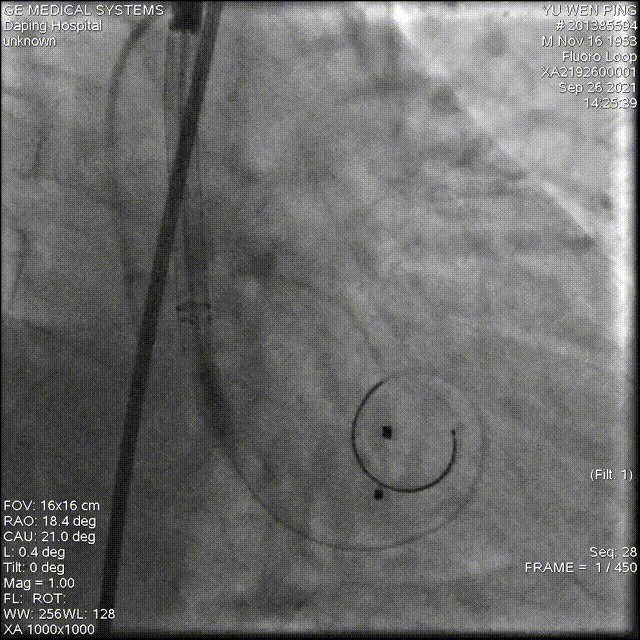

术中影像

以 Seldinger法穿刺右桡动脉,使用Pig造影导管行主动脉根部造影

20mm球囊预扩,有腰无漏

造影确定释放位置

释放成功,但存在中度瓣周漏,经20mm球囊后扩,造影见微量瓣周漏,较前明显好转